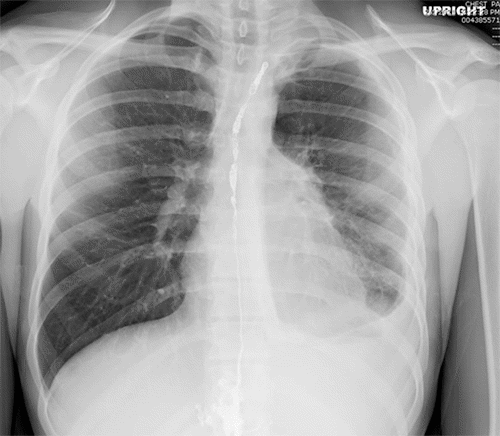

Chest tube drainage demonstrated a declining trend over the subsequent five days (Figure 11). Dietary advancement did not trigger an increase in output. Based on these findings, the chest tube was removed, and the patient was discharged home.

Figure 11. Chest X Ray, POD 5. Published with Permission

Improved left pleural effusion after repeat thoracic duct embolization